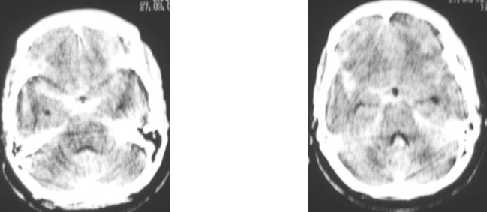

Subarachnoid hemorrhage :